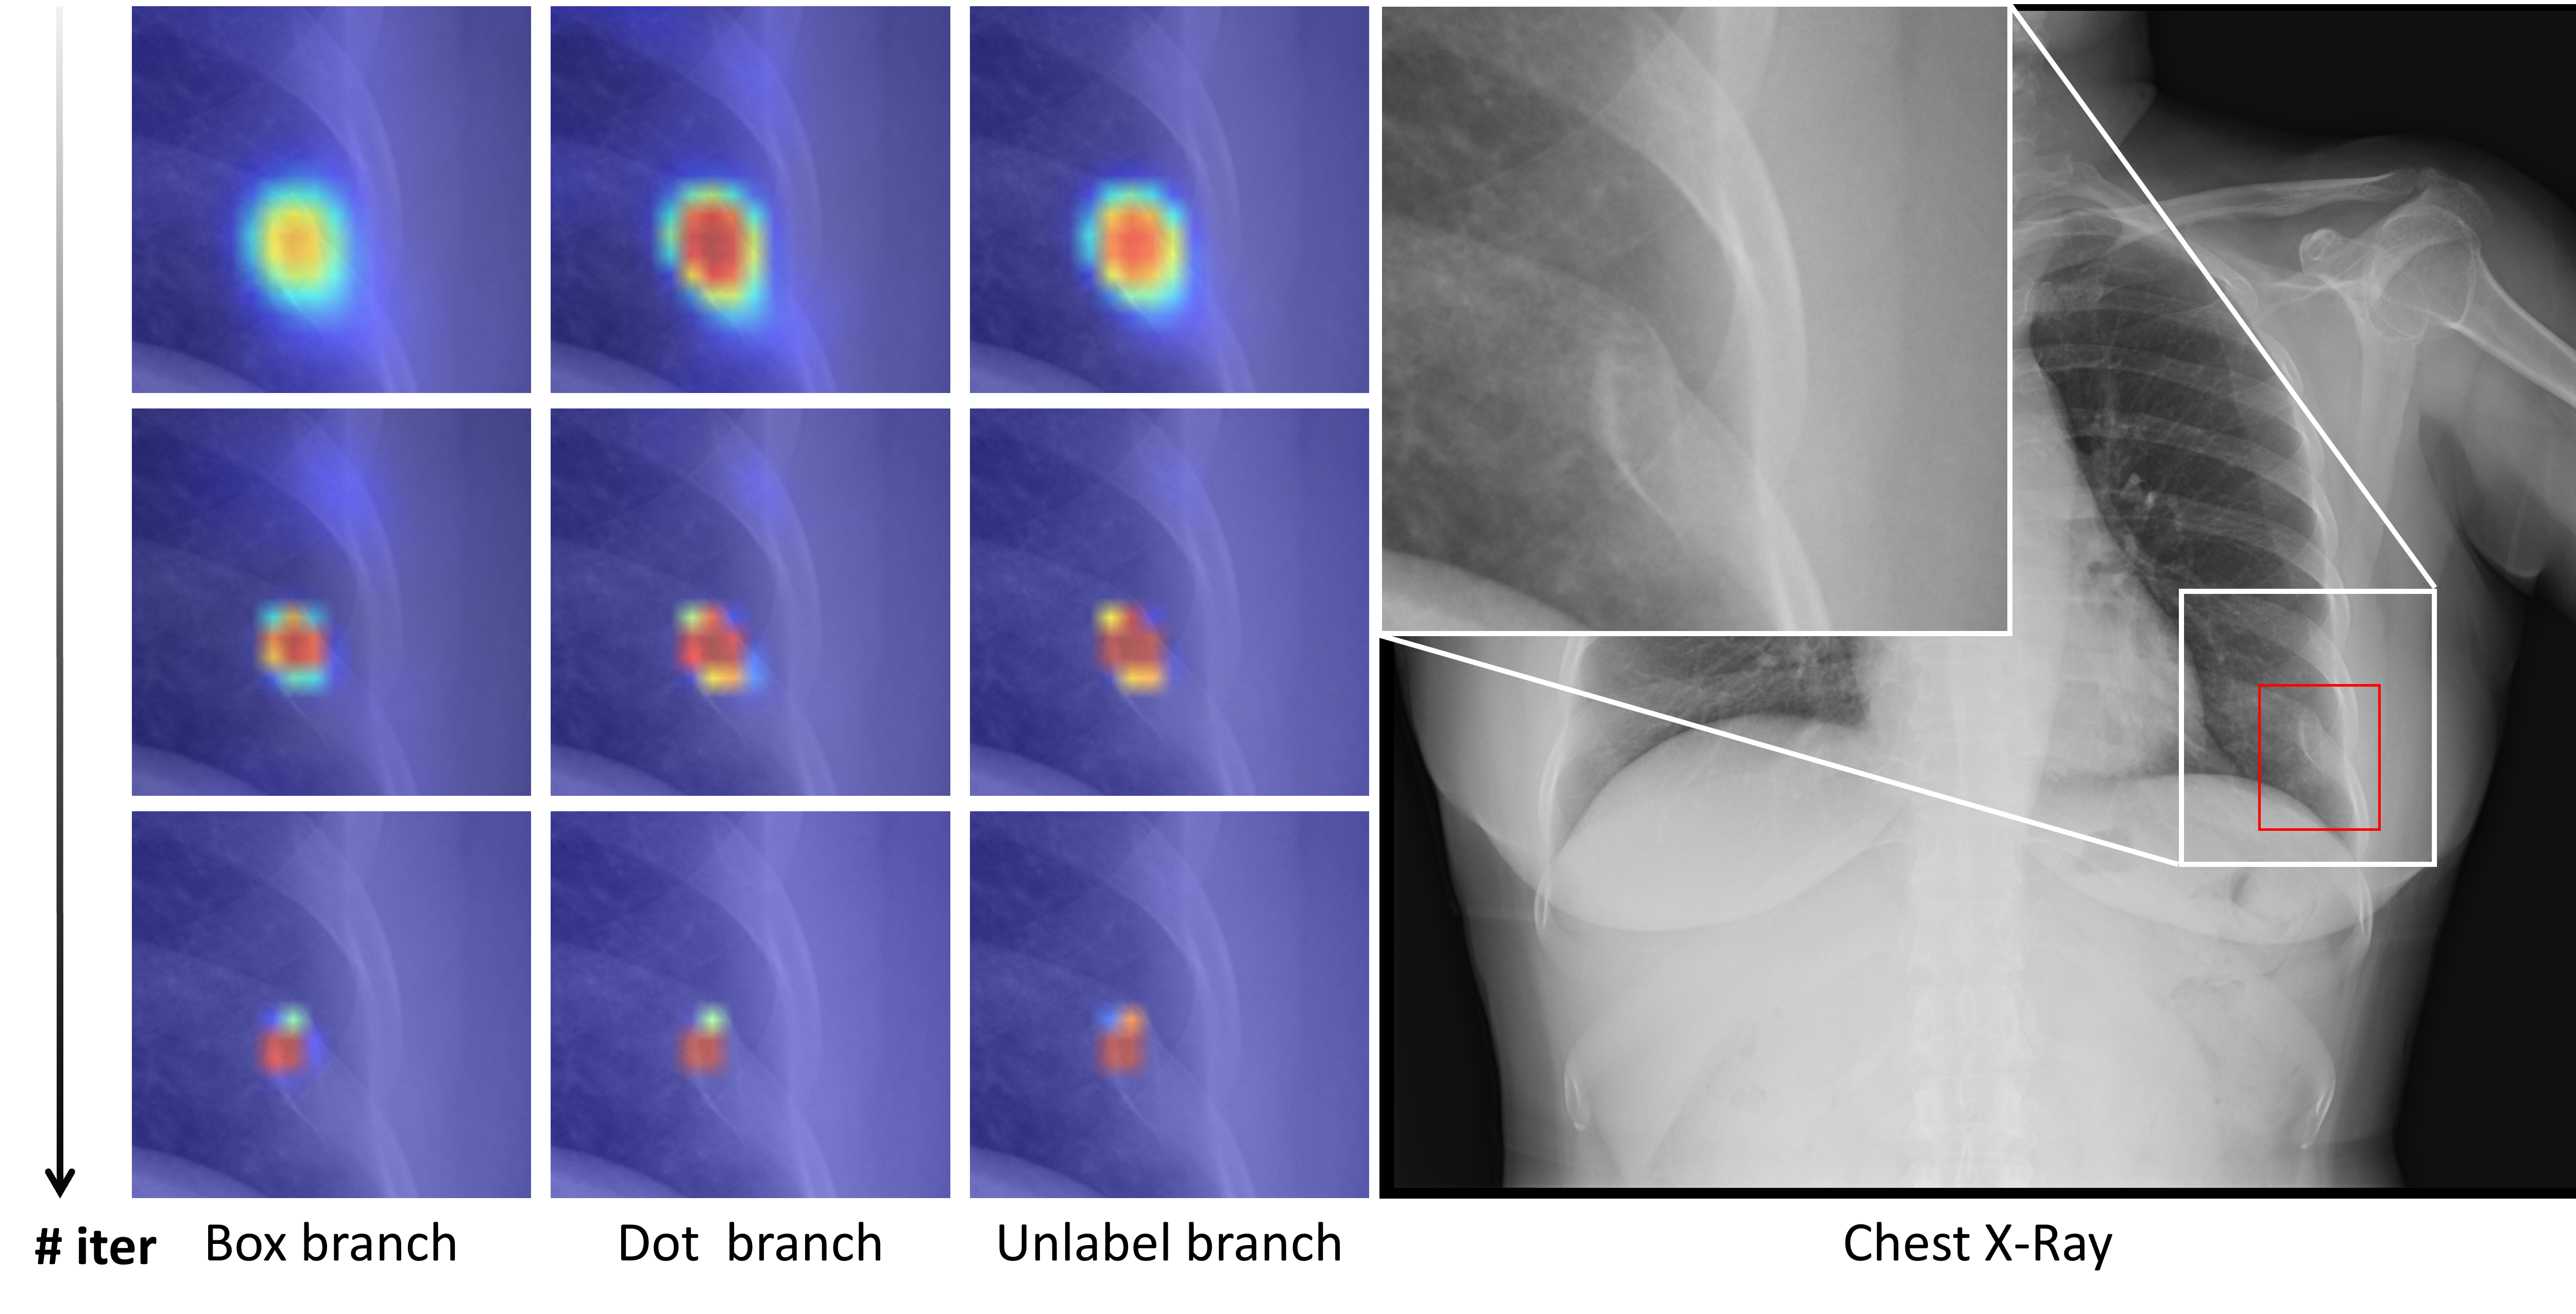

ORFNet

Deep Omni-supervised Learning for Rib Fracture Detection from Chest Radiology Images

Zhizhong Chai, Luyang Luo*, Huangjing Ling, Pheng-Ann Heng, Hao Chen

IEEE Transactions on Medical Imaging (IEEE TMI), 2024